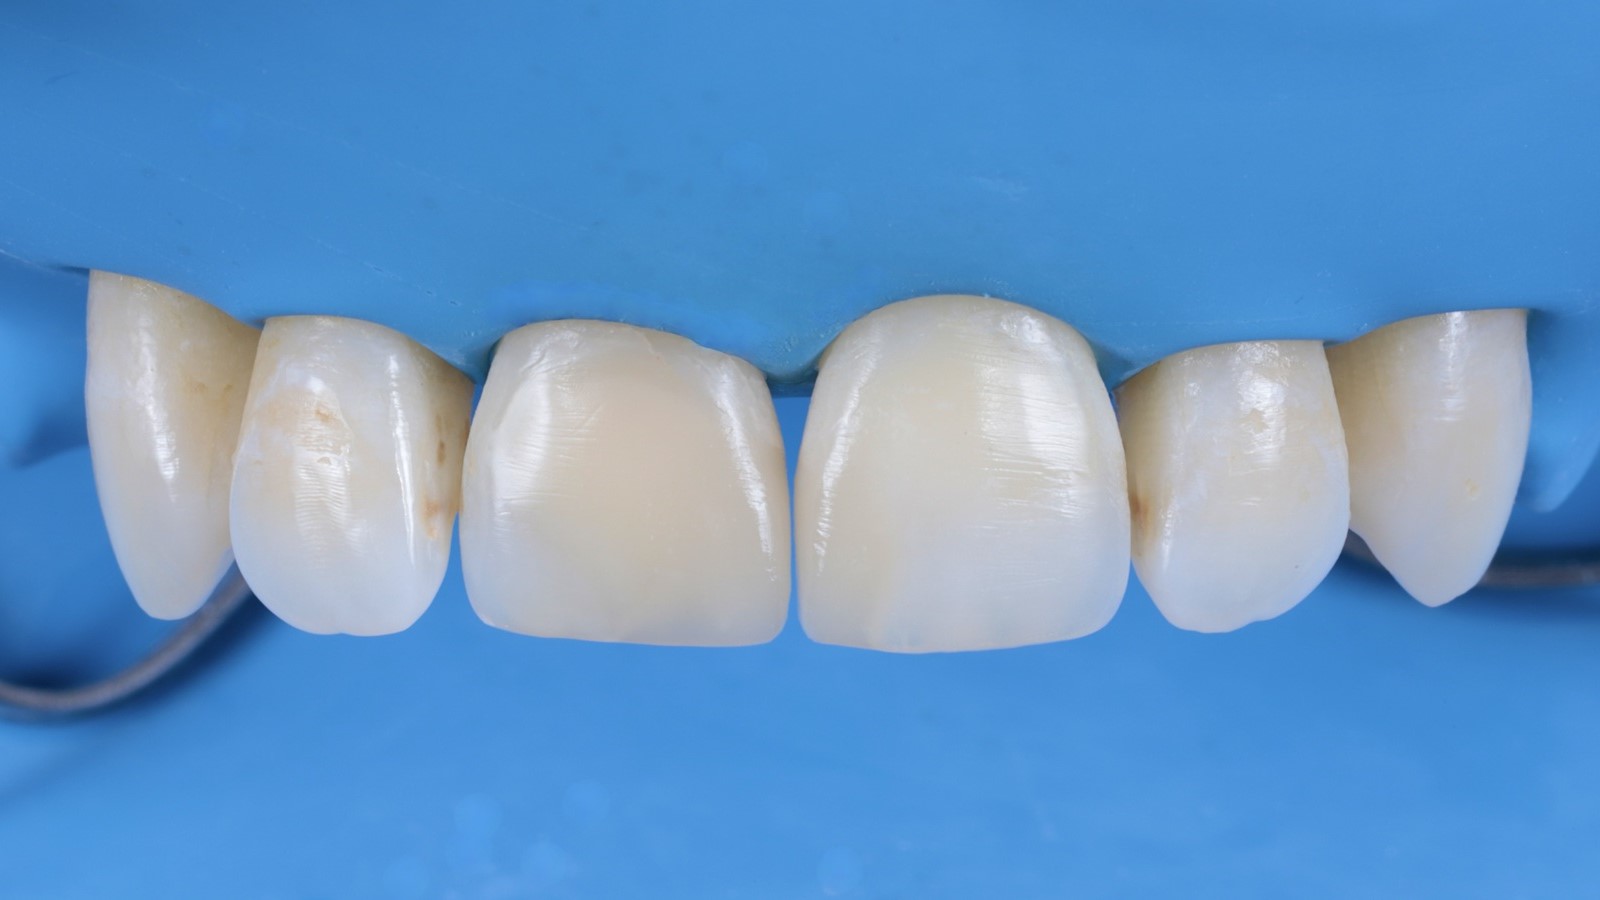

The restorations were polished while still under the dental dam.

The dam was removed, and the finally polished restorations were revealed.